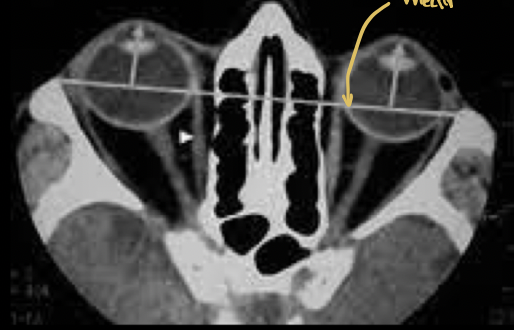

Como diagnosticar desprendimiento de retina

* Fondoscopia * US/TC * RM para evaluar neoplasias

Que estudio es y que se puede ver

USG que muestra retina doblada y brillante

De qué enfermedad sospechas?

Desprendimiento de retina

Que podemos ver en una RM y TC en desprendimiento de retina

* Hipersensidad * Fluido subretiniano * Neoplasias

Cuál es tu diagnóstico